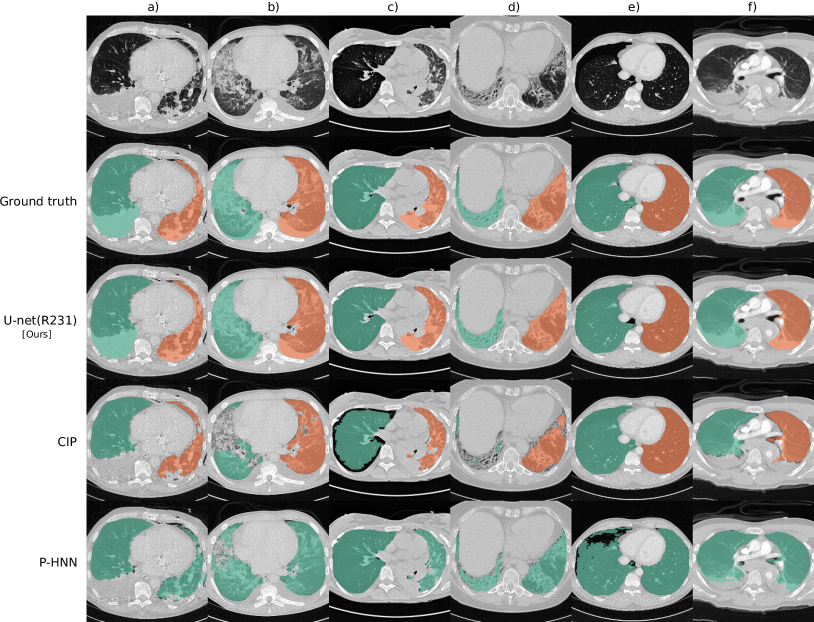

Refer to caption

Figure 2: Segmentation results for selected cases from routine data: Each column shows a different case. Row 1 shows a slice without lung masks, row 2 shows the ground truth, and rows 3 to 5 show automatically generated lung masks. Effusion, chest tube, and consolidations (a); small effusions, ground-glass and consolidation (b); over-inflated (right) and poorly ventilated (left), atelectasis (c); irregular reticulation and traction bronchiectasis, fibrosis (d); pneumothorax (e); and effusions and compression atelectasis (trauma) (f)

Models trained on routine data achieve improved evaluation scores compared to models trained on publicly available study data. U-net, ResU-net, and Deeplab v3+ models, when trained on routine data (R-36), yielded the best evaluation scores on the merged test dataset (All, n = 62). The U-net yields mean DSC, HD95, and MSD scores of 0.96 ±plus-or-minus\pm 0.08, 9.19 ±plus-or-minus\pm 18.15, 1.43 ±plus-or-minus\pm 2.26 when trained on R-36 [U-net(R-36)] and 0.92 ±plus-or-minus\pm 0.14, 13.04 ±plus-or-minus\pm 19.04, 2.05 ±plus-or-minus\pm 3.08 when trained on VISC-36 (R-36 versus VISC-36, p = 0.001, 0.046, 0.007) or 0.94 ±plus-or-minus\pm 0.13, 11.09 ±plus-or-minus\pm 22.9, 2.24 ±plus-or-minus\pm 5.99 when trained on LTRC-36 (R-36 versus LTRC-36, p = 0.024, 0.174, 0.112). This advantage of routine data for training is also reflected in results using other combinations of model architecture and training data. Table III lists the evaluation results in detail. We determined that the influence of model architecture is marginal compared to the influence of training data. Specifically, the mean DSC does not vary for more than 0.02 when the same combination of training and test set was used for different architectures (Table III). Compared to readily available trained P-HNN model, the U-net trained on the R-231 routine dataset [U-net(R-231)] yielded mean DSC, HD95, and MSD scores of 0.98 ±plus-or-minus\pm 0.03, 3.14 ±plus-or-minus\pm 7.4, 0.62 ±plus-or-minus\pm 0.93 versus 0.94 ±plus-or-minus\pm 0.12, 16.8 ±plus-or-minus\pm 36.57, 2.59 ±plus-or-minus\pm 5.96 (p = 0.024, 0.004, 0.011) merged test dataset (All, n = 62). For comparison with the CIP-algorithm, only volumes for which the algorithm did not fail were considered. On the merged dataset (All, N=62) the algorithms yielded mean DSC, HD95, and MSD scores of 0.98 ±plus-or-minus\pm 0.01 ,1.44 ±plus-or-minus\pm 1.09 ,0.35 ±plus-or-minus\pm 0.19 for the U-net(R213) compared to 0.96 ±plus-or-minus\pm 0.05, 4.65 ±plus-or-minus\pm 6.45, 0.91 ±plus-or-minus\pm 1.09 for CIP (p = 0.001, <<0.001, <<0.001). Detailed results are given in Table IV. Fig. 2 shows qualitative results for cases from the routine test sets and Fig. 3 shows cases for which the masks generated by the U-net(R-231) model yielded low DSCs when compared to the ground truth. We created segmentations for the 55 cases of the LOLA11 challenge with the U-net(R-231) model. The unaltered masks yielded a mean overlap score of 0.968 and with dense areas removed 0.977. Table V and Fig. 4 show results for tumour overlap on the 318 volumes of the Lung1 dataset. U-net(R-231) covered more tumour volume mean/median compared to P-HNN (60%/69% versus 50%/44%, p << 0.001) and CIP (34%/13%). Qualitative results for tumour cases for U-net(R-231) and P-HNN are show in Figs. 5b, c. We found that 23 cases of the Lung1 dataset had corrupted ground-truth annotation of the tumours (Fig. 5d). Fig. 5e shows cases with little or no tumour overlap achieved by U-net(R-231).